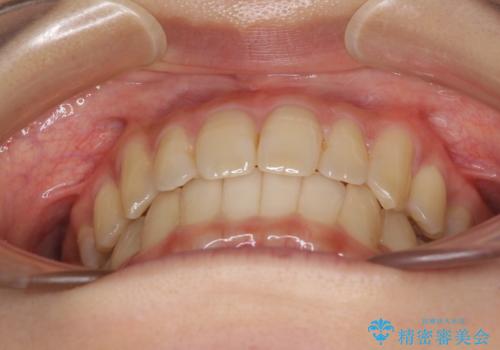

反対咬合が改善され、食いしばり癖もなくなり、顎関節の負担が軽減されました。

上顎骨を拡大したことで前歯に隙間ができ、1ヶ月ほど恥ずかしい時期がありましたが、しっかりとした咬み合わせに仕上がり、患者様には大変満足していただきました。